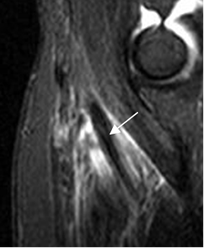

Fig 52 A. Bursitis del biceps.

RM sagital en STIR. Tendón con señal normal y rodeado por líquido, por bursitis.